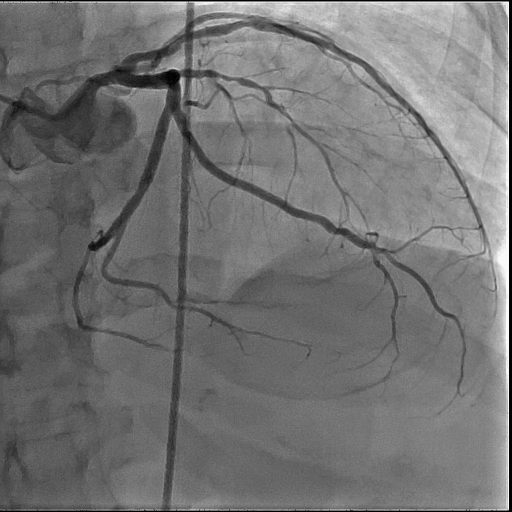

- Предназначена для диагностики и лечения не только патологии коронарных артерий, но и периферических сосудов

- Инновационный многоосевой механизм и передовые технологии обработки изображений для наблюдения за PCI устройствами обеспечивают четкую и точную поддержку обследования и лечения

Передовые технологии визуализации для визуализации сердцa и коронарных сосудов:

8" x 8" - предназначен в первую очередь для визуализации сердца